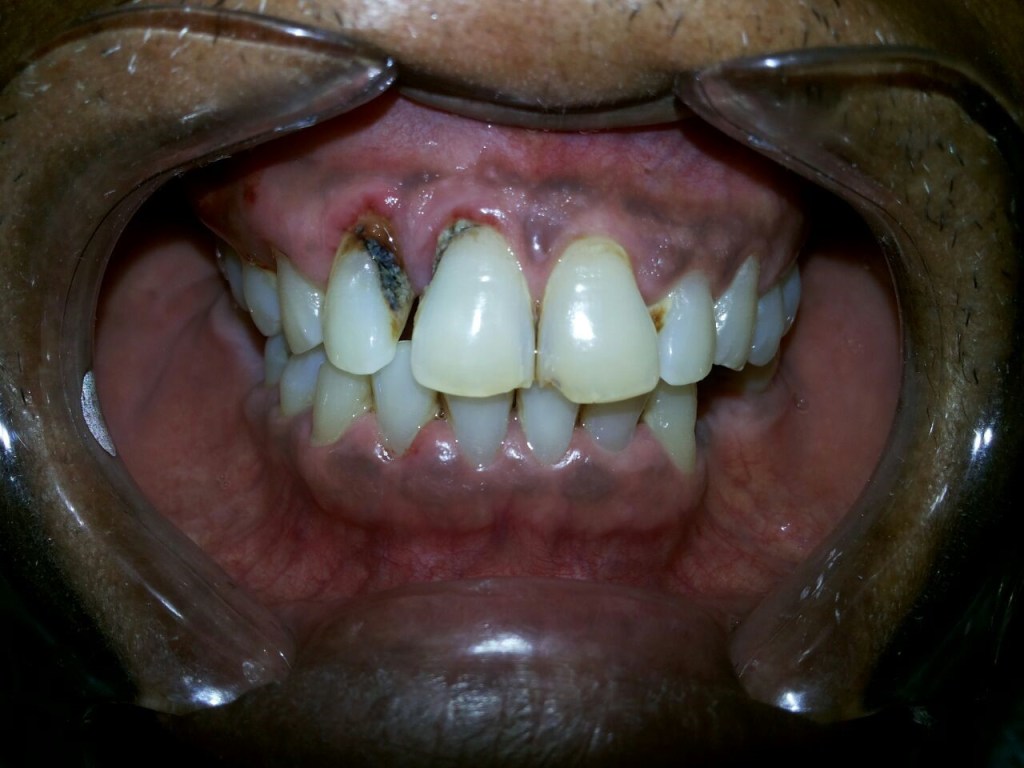

Melanosis perokok memiliki tampilan berupa pigmentasi kecokeltan, berbentuk irreguler asimetris, dengan tepian yang tidak tegas/ difus, flat dengan gingiva. Kondisi ini paling sering ditemui di gusi daerah labial gigi seri dan gigi taring, sera mukosa bukal. Orang dengan melanosis perokok pada umumnya memiliki bau mulut khas perokok.

Terdapat kondisi lain yang tampilan menyerupai melanosis perokok, yakni pigmentasi fisiologis. Pewarnaan mukosa ini merupakan suatu kondisi yang normal pada kelompok rasial tertentu, pada umumnya pada kelompok dengan warna kulit gelap. Kondisi ini dapat dibedakan dengan melanosis perokok melalui anamnesa bahwa pewarnaan yang terjadi dalam rongga mulut sudah ada sejak lahir, sehingga tidak berhubungan dengan kebiasaan merokok.